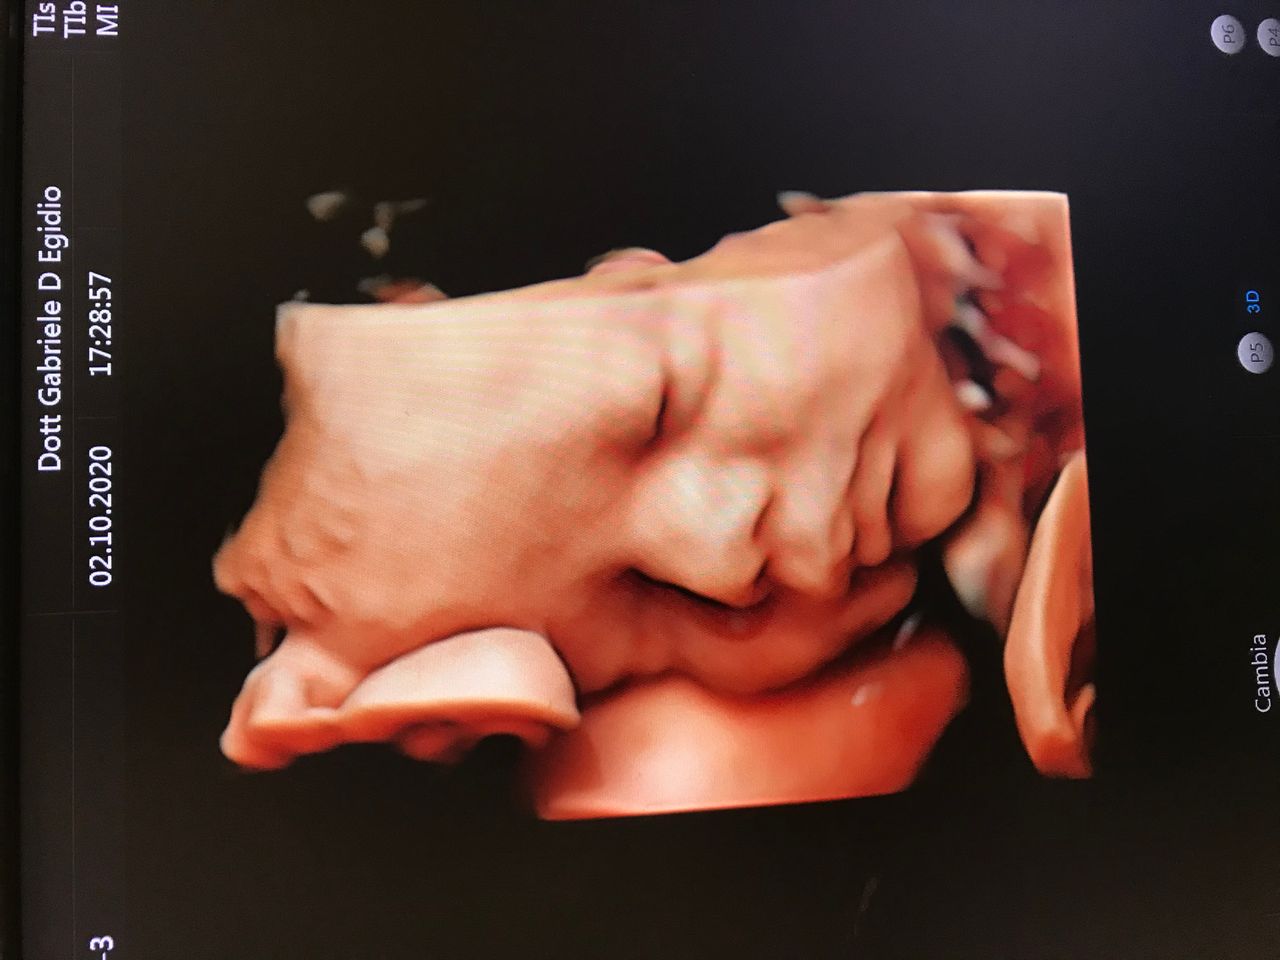

Per quanto riguarda la mia esperienza mi ha seguito la prima gravidanza che non è andata bene devo dire molto scrupoloso nel suo lavoro mi ha monitorato sia di persona e sia a distanza fino a quando le beta non sono tornate normali. Poco dopo mi ha seguito la seconda gravidanza che è andata benissimo anche in questo caso molto professionale e scrupoloso, anche nelle visite in routine è così mi sento di consigliarlo

Ha salvato mio figlio, il MIGLIORE. Questo si che è un Dottore con un cuore. Oltre ad essere un ottimo professionista e’ un dottore vero che ascolta il paziente e lo comprende profondamente, umile e sorprendentemente bravo in un mare di impreparati veri!!!!

Ottimo professionista! Sono riuscita ad avere una gravidanza dalla prima visita con il dottore, dopo che erano mesi di tentativi ed alcuni professionisti mi avevano detto che le probabilità erano molto basse (ovviamente non era vero). Al primo tentativo, con i consigli e i monitoraggi del dottor D'Egidio, sono riuscita in una gravidanza che sembrava impossibile.